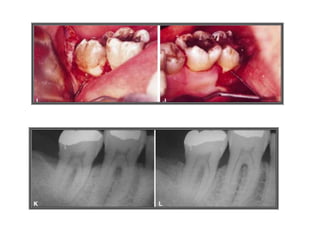

TRATAMENTO DAS LESÕES

ENDOPERIODONTAIS

Hemisseccção

DEL RIO, 1996